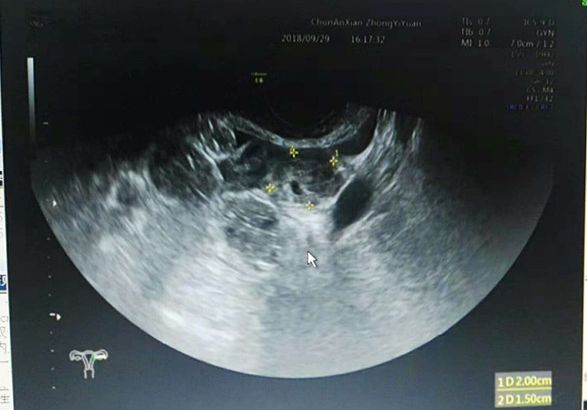

近日,一名38岁女性患者,1个月前在某医院行人流术后出现阴道出血,腹痛,怀疑人流后残留来县中医院妇科门诊就诊。经妇产科仔细检查,结合尿HCG700mIU/ml,超声检查左附件区混合回声团块,最终考虑并非人流后残留,而是存在宫外孕现象,当即给予收住入院。这种宫内孕合并宫外孕的病例非常少见,幸好中医院妇产科临床医生谨慎,超声医生检查仔细,手术及时,一起合作解除了病魔。

复合妊娠是指同时发生在2个或以上种植部位的妊娠,以宫内外复合妊娠常见,在自然妊娠中罕见,发生率约1/30000,随着辅助生殖技术广泛开展,发生率明显增高,达1%左右。宫内外复合妊娠中最常见类型为宫内合并输卵管妊娠约占88.2%,超声是主要诊断方法。